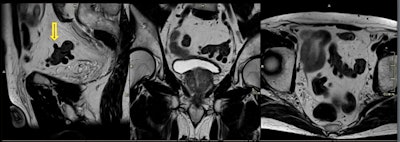

In their analysis, they identified the following genitourinary incidental findings:

- Utricular cysts: midline area of focal dilatation that occurs within the prostatic utricle

- Cowper's gland duct cyst: midline oval structure at the penile base adjacent to the ventral aspect of the proximal bulbous urethra

- Seminal vesicle hemorrhage: hyperintense signal at precontrast T1-weighted MRI is indicative of hemorrhage in the seminal vesicles as well as in the prostate

- Hydrocele: acquired or congenital serous fluid collections between the layers of the tunica vaginalis surrounding a testis or spermatic cord